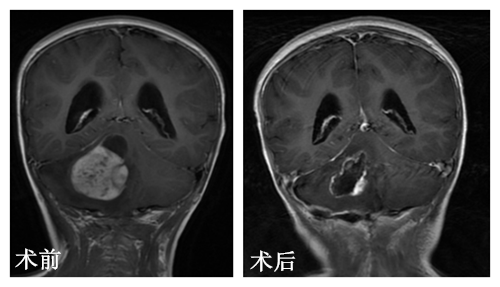

为明确诊断,李家夫妇带着女儿来到广州求治,广东三九脑科医院小儿神经外科进行MR平扫及增强,提示后颅窝占变,以右侧小脑半球为主,且瘤脑界面清晰。

小儿神经外科杨宝应主任及其团队进行术前讨论,彤彤的手术指征明确,无手术禁忌症。在完善术前准备之后,由杨宝应主任主刀,予显微镜下为彤彤施行了右小脑占位性病变切除术,成功把彤彤脑袋里大小约2*2.5cm的灰白色肿瘤组织切除下来。术后一天,彤彤恢复意识,无发烧感染,头部四肢活动良好,于是辅以放射治疗。术后病理结果:髓母细胞瘤。